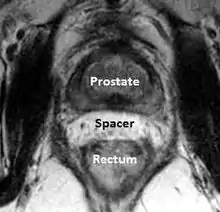

A new method to reduce rectal radiation injury in prostate cancer patients involves the use of an absorbable spacer placed between the prostate and rectum.

Such spacers are commercially available in some regions, and are undergoing clinical trials in others.[28] By temporarily altering the anatomy these products have the potential to allow for improved cancer targeting while minimizing risk to neighboring healthy tissues. Prostate rectum spacers should be compatible with all prostate cancer radiotherapy treatments including 3D conformal, IMRT and stereotactic radiation and brachytherapy.